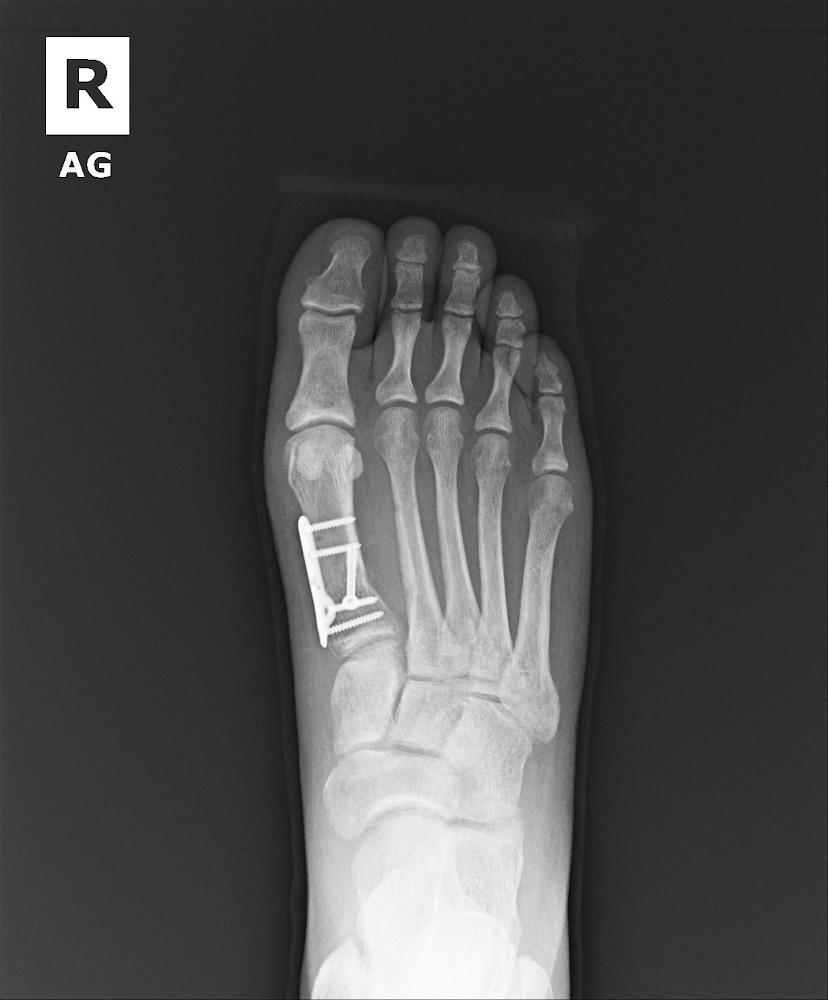

From www.reddit.com

Xray for bunionectomy and first metatarsal osteotomy r/bunions Bunion Metatarsal Bunions develop at the mtp joint. As a result of a bunion formation, a condition called hallux valgus may develop which is when the big toe deviates or points towards the other toes. This inflammation is caused by the bony. A bunion is a deformity of the metatarsophalangeal (mtp) joint at the base of the big toe. Bunion a bunion. Bunion Metatarsal.